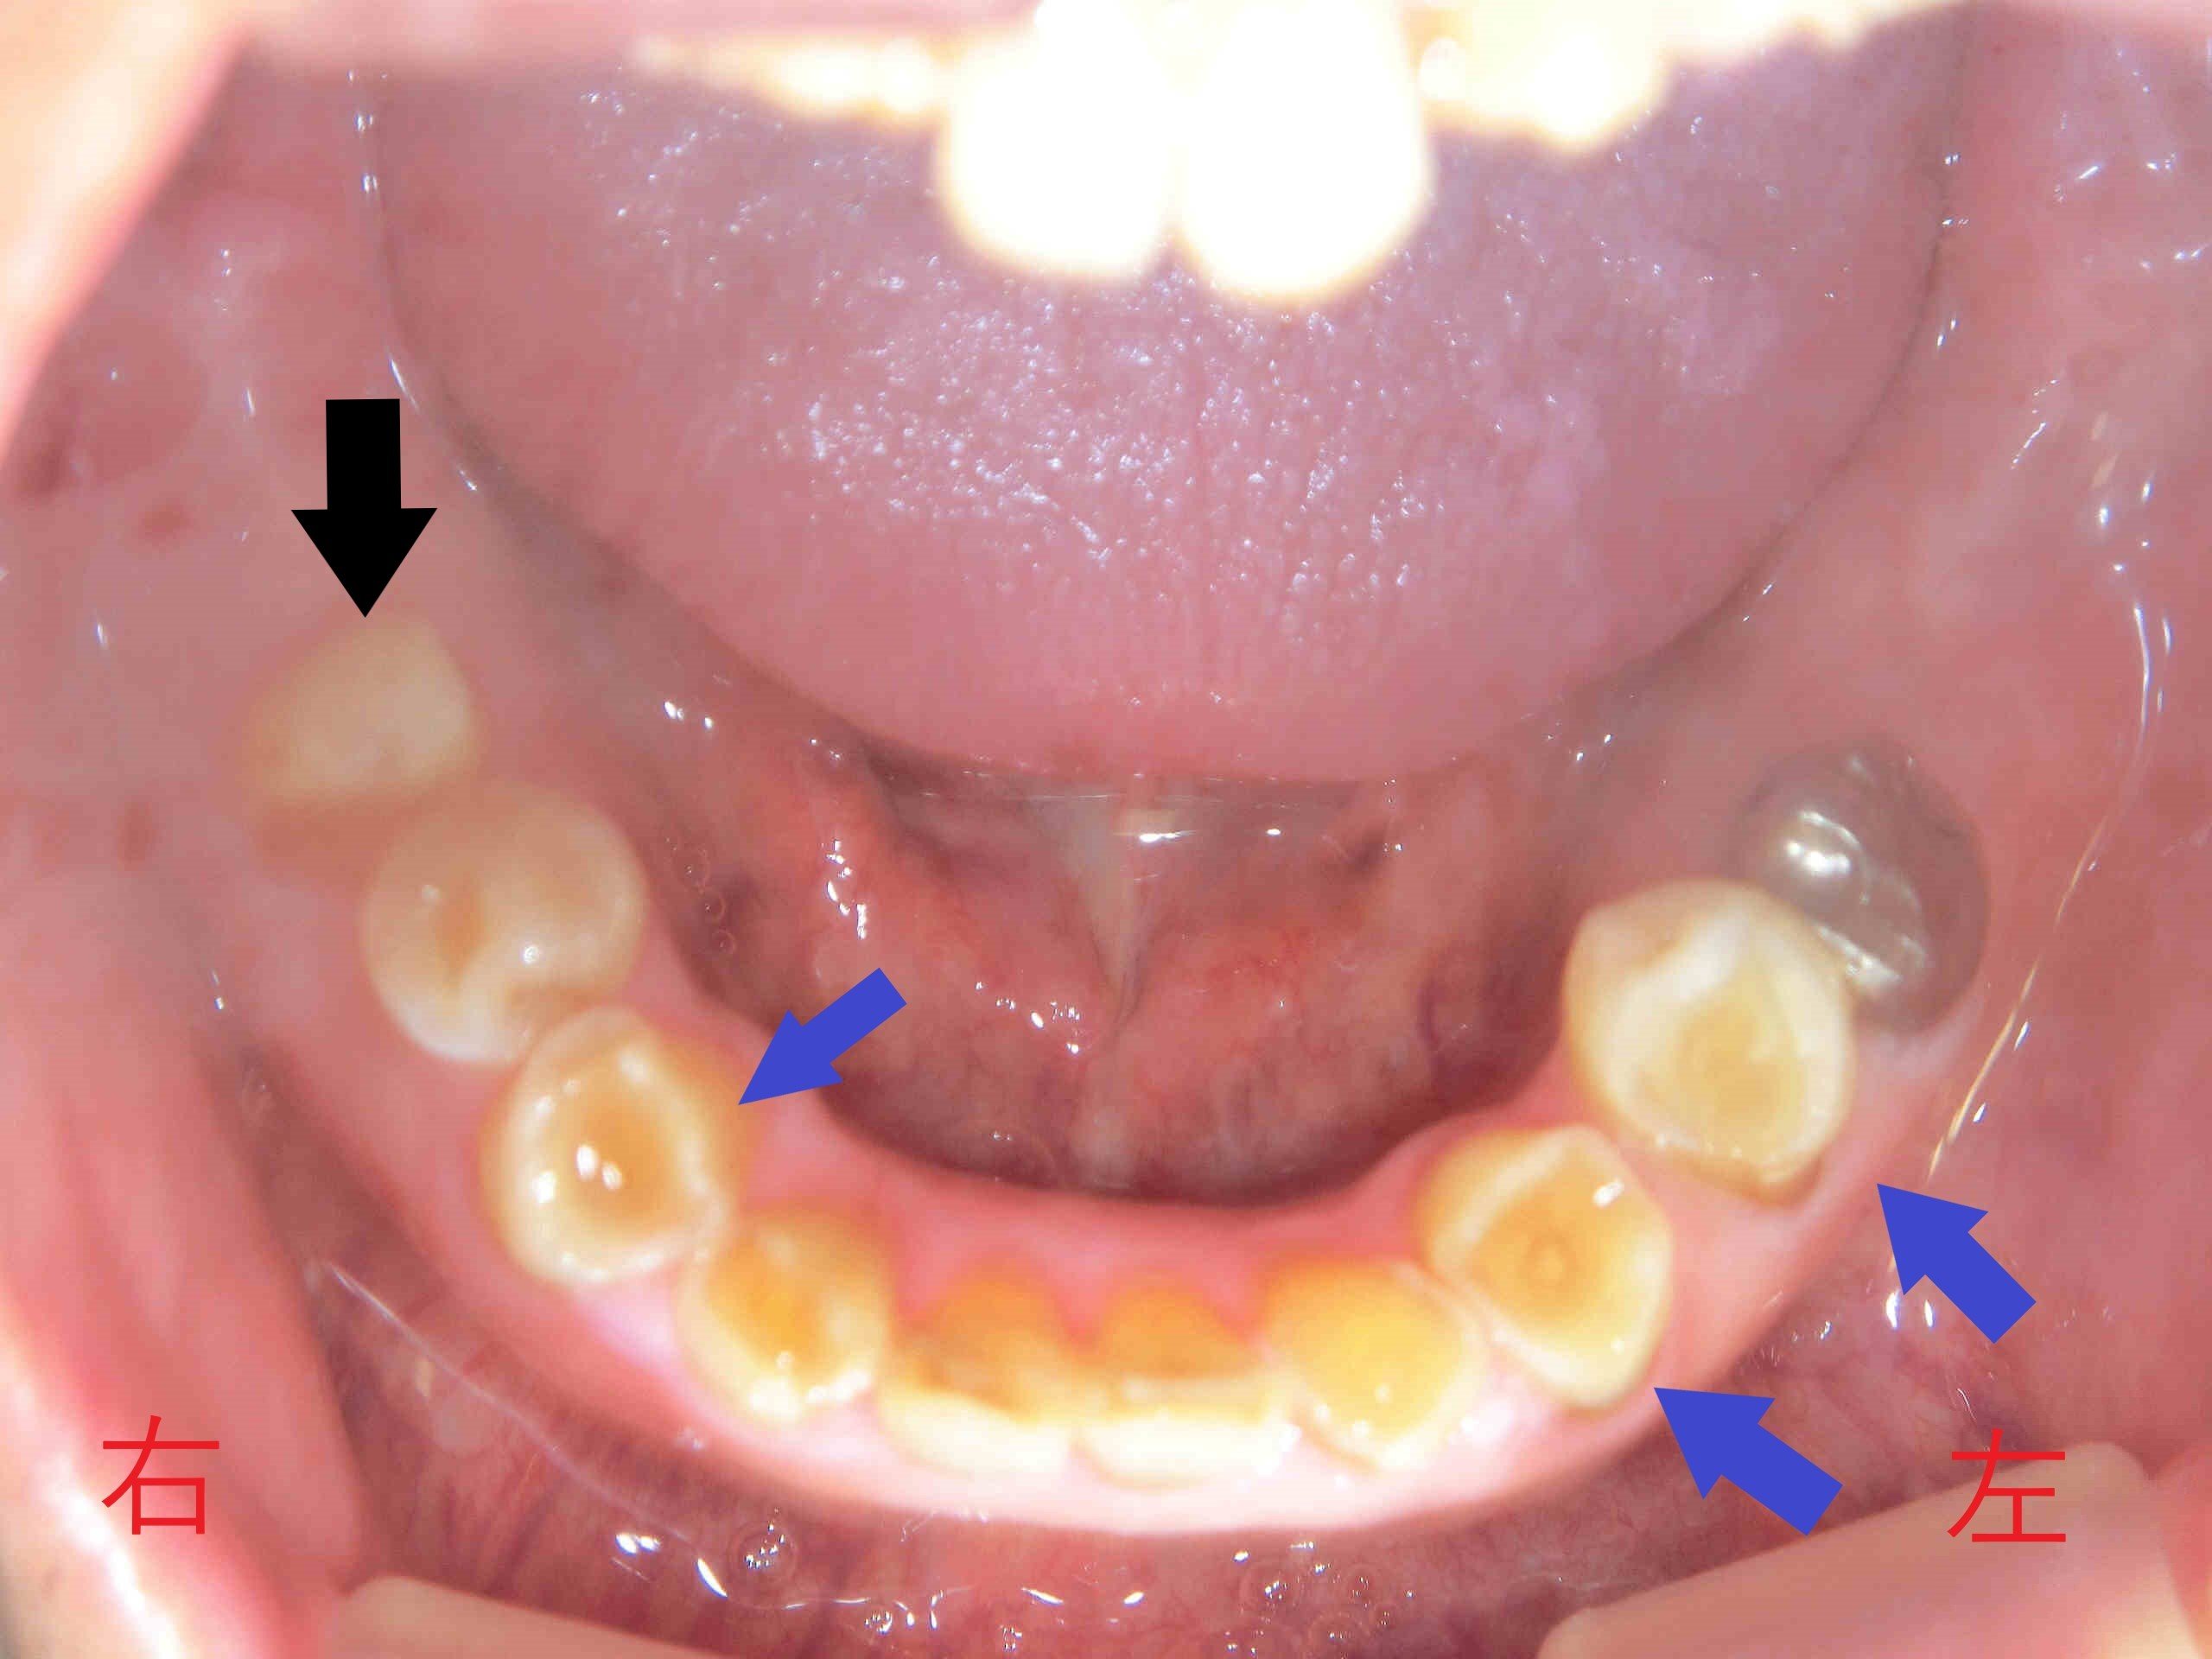

左上は治療前(初診時)に近い状態の上顎を下から見上げた写真、右上は同じ状態の下顎を上から見た写真です。いずれも青色矢印の歯をご覧ください。歯ぎしりや食いしばりのために歯がすり減り、歯の表面が陥没している様子が観察されます。